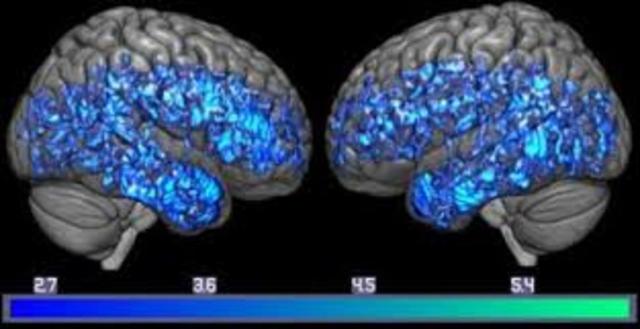

• Neuroimagenología y la Neurofisiología moderna

Neuroimagenología y la Neurofisiología moderna

Estas disciplinas aportan tecnologías importantes que han propiciado un gran avance en la investigación en neurociencias

• Resonancia Magnética Funcional

Resonancia Magnética Funcional

La Resonancia Magnética Funcional permite medir el metabolismo regional del cerebro.